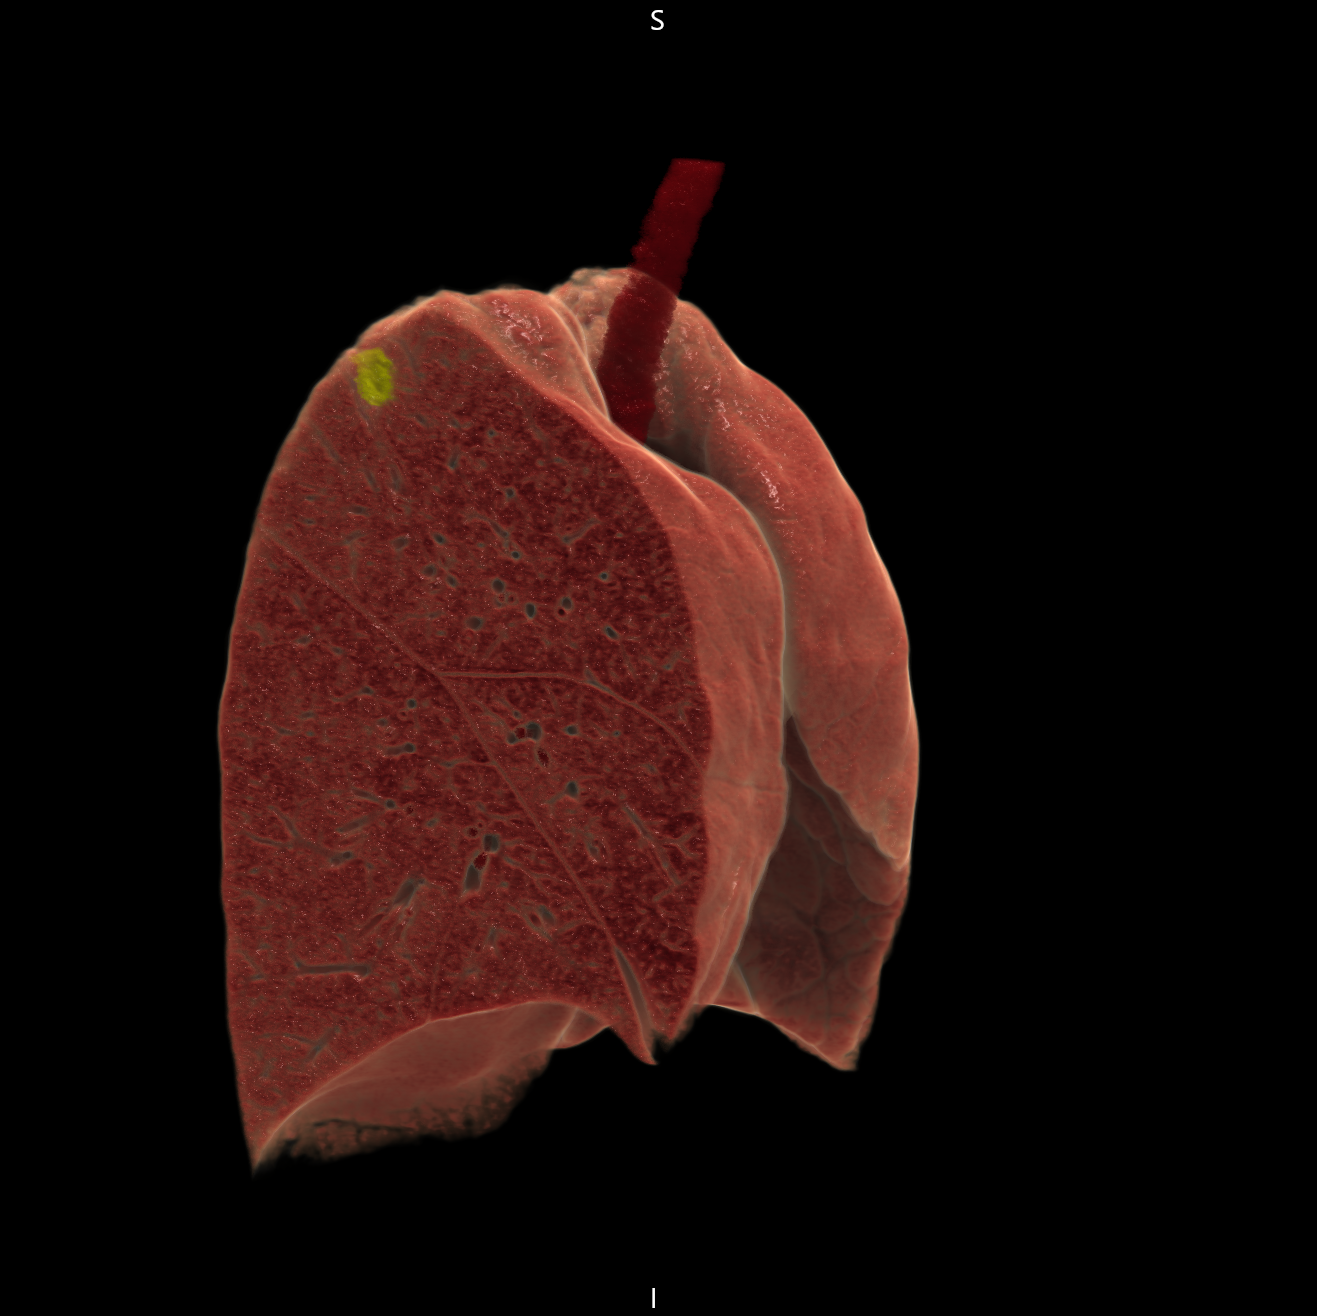

PCCTの肺がん疑い症例

c 全肺野3D画像(黄色部が病変)